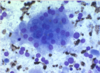

what is shown here

neutrophilic inflammation

bacteria seen